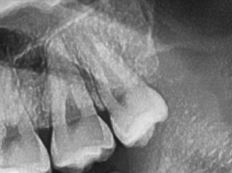

#18,28,38,48 사랑니 발치

구강 외과 전문의가 당일 발치했습니다.